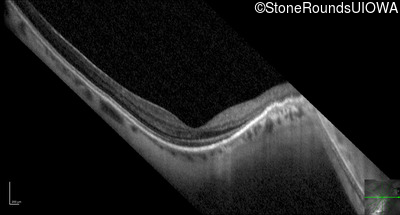

OCT Stack